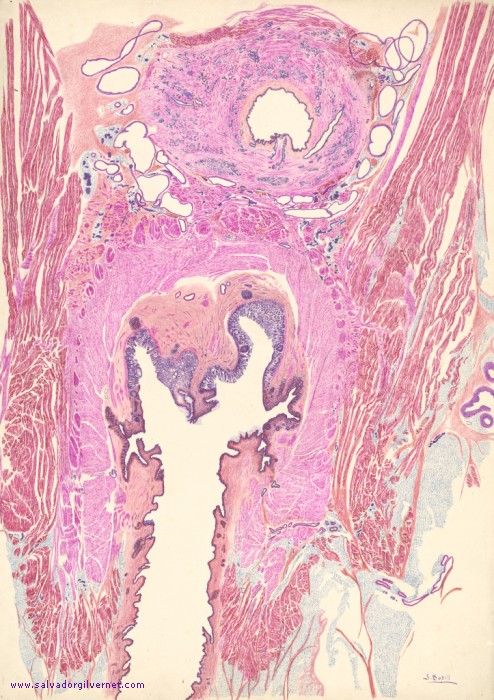

Pelvis y periné

• Serie K4

• Corte histotopográfico coronal oblicuo

Varón de 5 años

Tinción HE

• J. Bofill.  ca. 1944

• Tinta china sobre papel.  67 x 48 cm.

• Uretra prostática dilatada debido a la presencia de un siringocele.

Próstata. Uretra prostática. Veru montanum. Conductos eyaculadores. Cresta uretral. Fibras ventrales de la porción craneal del esfínter uretral externo. Haces neurovasculares periuretrales y nervios hemorroidales. Fascia endopélvica. Aponeurosis de Denonvilliers. Músculos elevadores del ano. Canal anal y esfínter externo del ano.